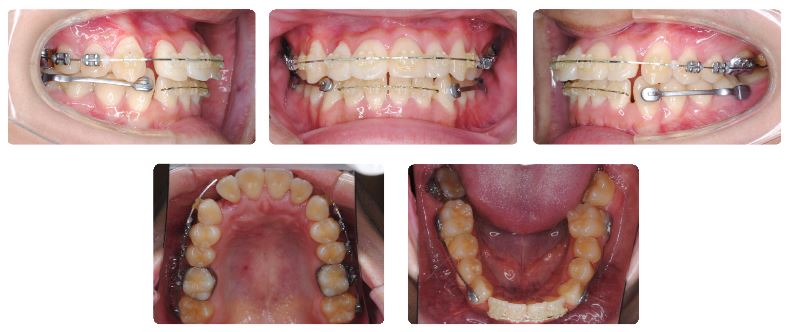

2症例目は10代後半の女性です。

上顎の治療を先行しています。現在上顎左側の小臼歯のねじれを改善している最中です。

上顎の小臼歯のねじれが改善されてワイヤーもしっかりとしたものに交換した時点で、下顎にカリエールモーションを装着しました。

カリエールモーション装着から3か月後の状態です。

下顎前歯にスペースが認められるようになりました。また下顎前歯も内側に入ってきています。

カリエールモーションの使用期間は4か月でした。